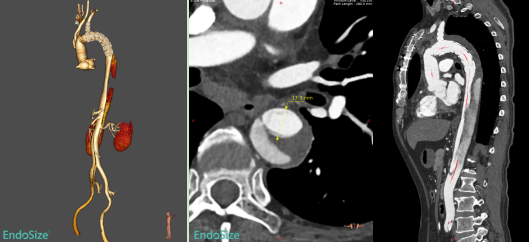

术后复查的CTA

术后复查CTA进一步证实,患者残余夹层覆膜支架段内膜破口有效覆盖,假腔无血流,远端真腔扩张良好。